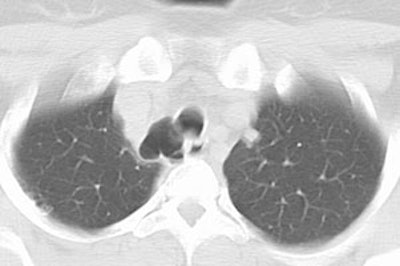

Tracheal diverticulum: The patient shown below was being evaluated for active pulmonary tuberculosis and was incidentally discovered to have a tracheal diverticulum. Note the slightly irregular wall of the diverticulum which can be seen in almost one-third of cases. Click here to view cine image which nicely confirms communication with the trachea. |